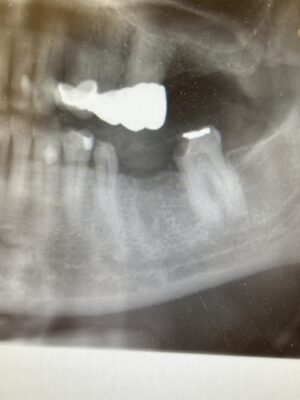

I have a non-implant case that im having issues with pt management so i thought id ask y’all what to do. I did bridge for pt from 18-20 and ext #19 in 2020. I saw her feb 10 2023 b/c she claims that the ext of 19 hurts and her other dentist stated i left a root. Im going to also include a pano i captured after ext showing how small the piece i left was and I dont think this causing her pain but she wants to argue and potentially sue so my district manager agreed Id remove the zirconia bridge, attempt to remove the piece of root and make a new bridge. Im trying to figure out if this is the source of her pain and if not what is it.

• The zoomed in photo of the bridge is after I recently extracted 19 and placed the temporary bridge on 3/2020. I just zoomed in so we can see how little of the mesial root apex is present. The pano is from Feb of this year. Removing the piece of root apex will suck. 😫

• This was the best I could do after drilling for 1/2 hour and taking 4 other panos. Cross our fingers her pain goes away.